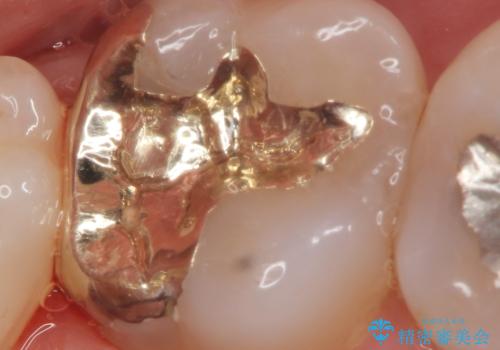

ゴールド治療について

上顎大臼歯など目に触れにくく大きな力のかかる部位は、ゴールドによる修復をお勧めすることがあります。

PGA(ゴールド)クラウン、インレーの注意事項(リスク・副作用など)

- インレーおよびクラウンは脱離するリスクがあります

- 形成量はセラミックより少ないですが、歯の形成、修復後に歯に症状が出ることがあります

- 自費診療(保険適用外治療)となります